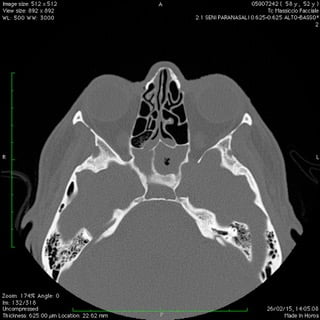

Anche nelle sinusiti la peculiare morfologia anatomica delle strutture coinvolte, cavità ossee, consente nella maggior parte dei casi latenze di esordio molto ritardate rispetto il primitivo insorgere patologico palesandosi così in avanzate fasi di compromissione .

Nelle forme croniche, cioè di malattia stabile nel tempo, i seni paranasali diventano “ siti di decantazione”, ovvero di ristagno e moltiplicazione,per germi di vario genere dando vita così ad un persistente primario serbatoio contaminante sia le vie aeree che quelle digestive.